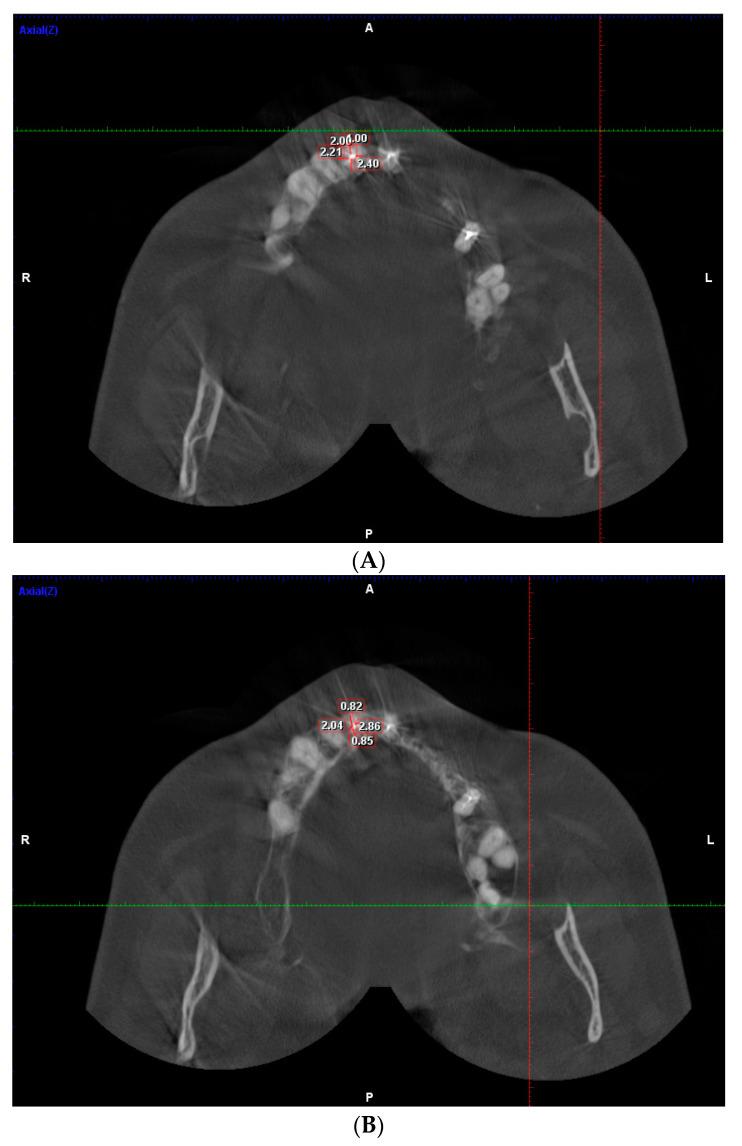

Three hundred CBCT scans for three age groups were analyzed to study the dentinal thickness pre- and post-endodontic treatment. The dentinal thickness (DT) was measured along the buccal, mesial, distal, and lingual/palatal walls from the inner surface of the root canal to the outer surface in mm. Statistical analysis was set at 0.05.

分析三个年龄组的300例CBCT扫描,以研究根管治疗前后的牙本质厚度。牙本质厚度(DT)以毫米为单位,沿着根管内表面至外表面的颊侧、近中、远中以及舌侧/腭侧壁进行测量。统计学分析设定为0.05。